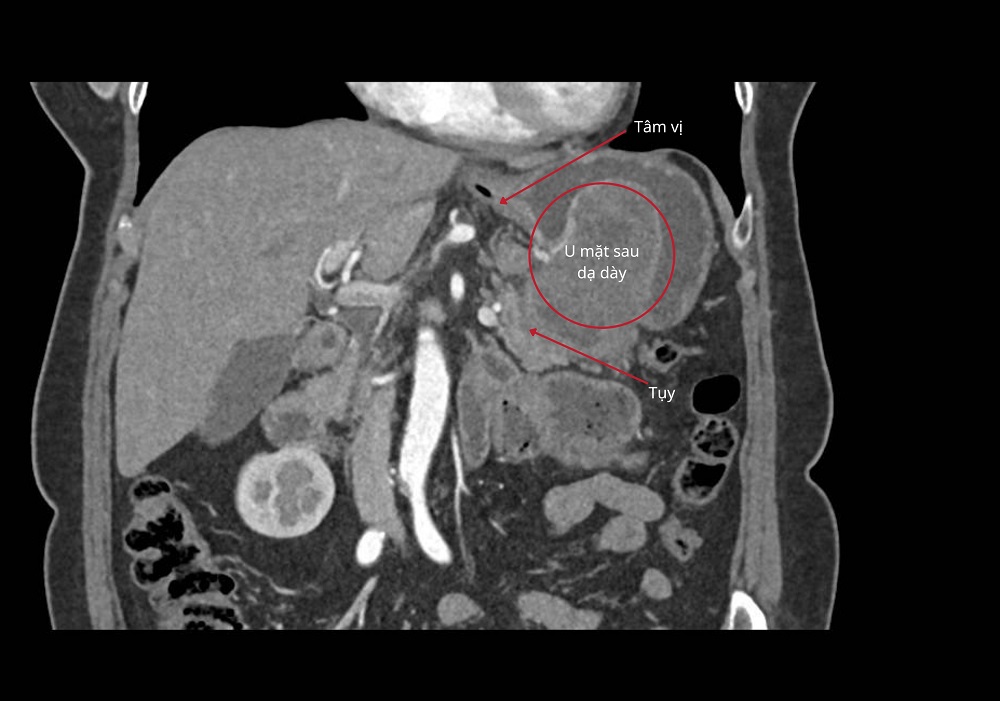

Khối u GIST dính vào tụy và mặt sau dạ dày gần tâm vị

Theo ThS.BS CKII Phan Văn Thái - Trưởng khoa Ngoại Tổng quát (Bệnh viện FV), khối u mô đệm (GIST) của bệnh nhân H.T có kích thước khoảng 5x5x7cm. Tuy nhiên, điều đáng lo ngại là ở vị trí và cấu trúc phức tạp của nó: khối u nằm khuất ở mặt sau dạ dày, sát tâm vị, dính vào bề mặt tụy và đã hoại tử khoảng 30% - những yếu tố khiến việc can thiệp trở nên đặc biệt thách thức.